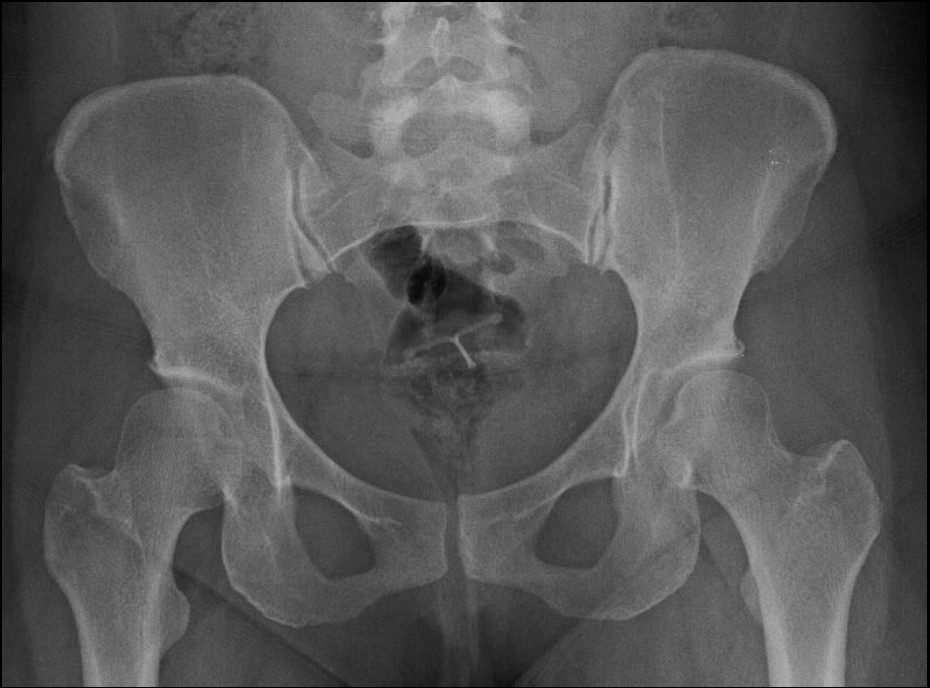

Imagerie de la hanche :  variantes et anomalies fréquemment asymptomatiques

Musculo-squelettique Hanche Journée d'imagerie des CUSL